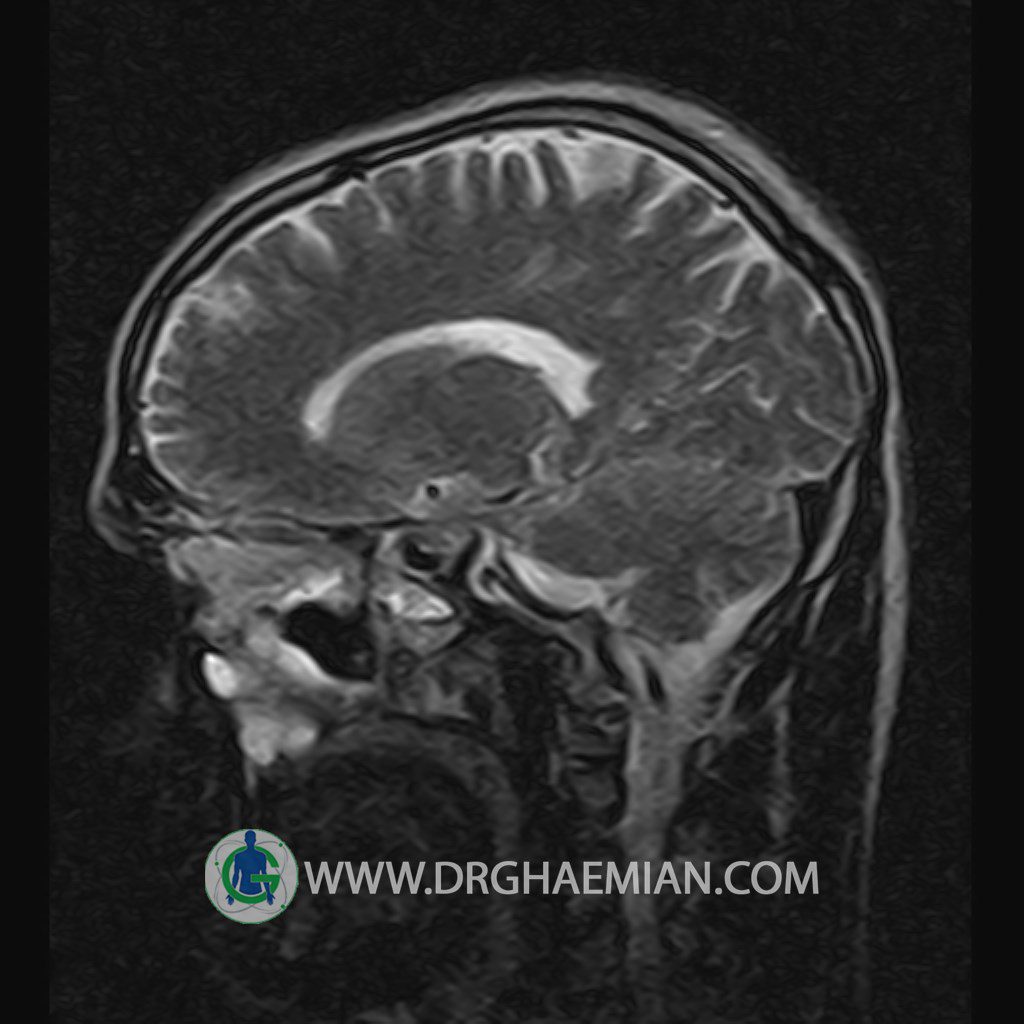

پزشکان اغلب از تصویربرداری ام آر آی برای تشخیص و درمان عارضه های پزشکی که فقط با استفاده از اشعه ایکس یا میدان مغناطیسی و امواج رادیویی قابل مشاهده است، استفاده می کنند. دستگاه ام آر آی تصاویر دقیق از ساختار های داخلی بدن ایجاد می کند. در این کیس یک میکروآدنوم در هیپوفیز بیمار مشاهده می شود.

HYPOPHYSIS MRI

(with and without contrast)

Technique: Axial , coronal T1 , Axial , coronal , sagittal T2 , Axial, coronal T1 post Gd & 64 dynamic thin coronal slices.

The infundibulum is centered and of normal size .

The optic chiasm and suprasellar spaces appear normal .

The cavernous sinus and imaged portions of the internal carotid artery and carotid siphon are unremarkable .

Evaluable portions of the neurocranium show no abnormalities .

The sphenoid sinus is clear and pneumatized .

Imaging of the hypothalamus after contrast medium administration was normal.

– Small hypoenhancing mass lesion ( 3 x 4 mm ) in posterior of pituitary stalk suggestive for micro adenoma

– Mucosal thickening in ethmoid & maxillary sinuses

is seen